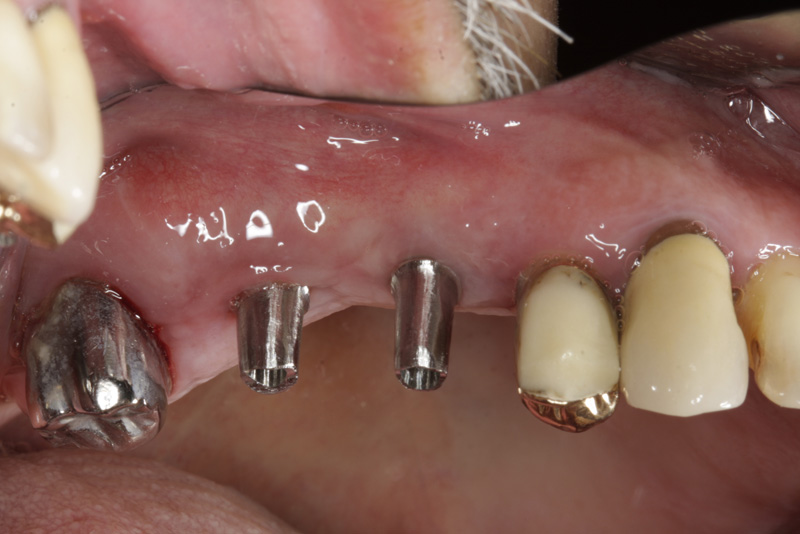

Bezzubá čelist je hlavní indikací pro ošetření pomocí implantátů. Zejména celkové zubní náhrady v dolní čelisti mají velice nízkou stabilitu a držení díky velkému úbytku kosti.

S pomocí zubních implantátů můžeme díky různým kotevním systémům (třmeny, kulové hlavy, Locatory) zajistit stabilitu a držení protézy nebo při použití většího počtu implantátů zhotovit pevné náhrady – můstky nalepené nebo našroubované na pevno na implantáty.

S těmito typy náhrad můžeme dosáhnout perfektní funkci, výbornou estetiku, fonetiku a současně zajistit u pacienta možnost dobré hygienickou péče a čištění, která je pro životnost implantátů velice důležitá.